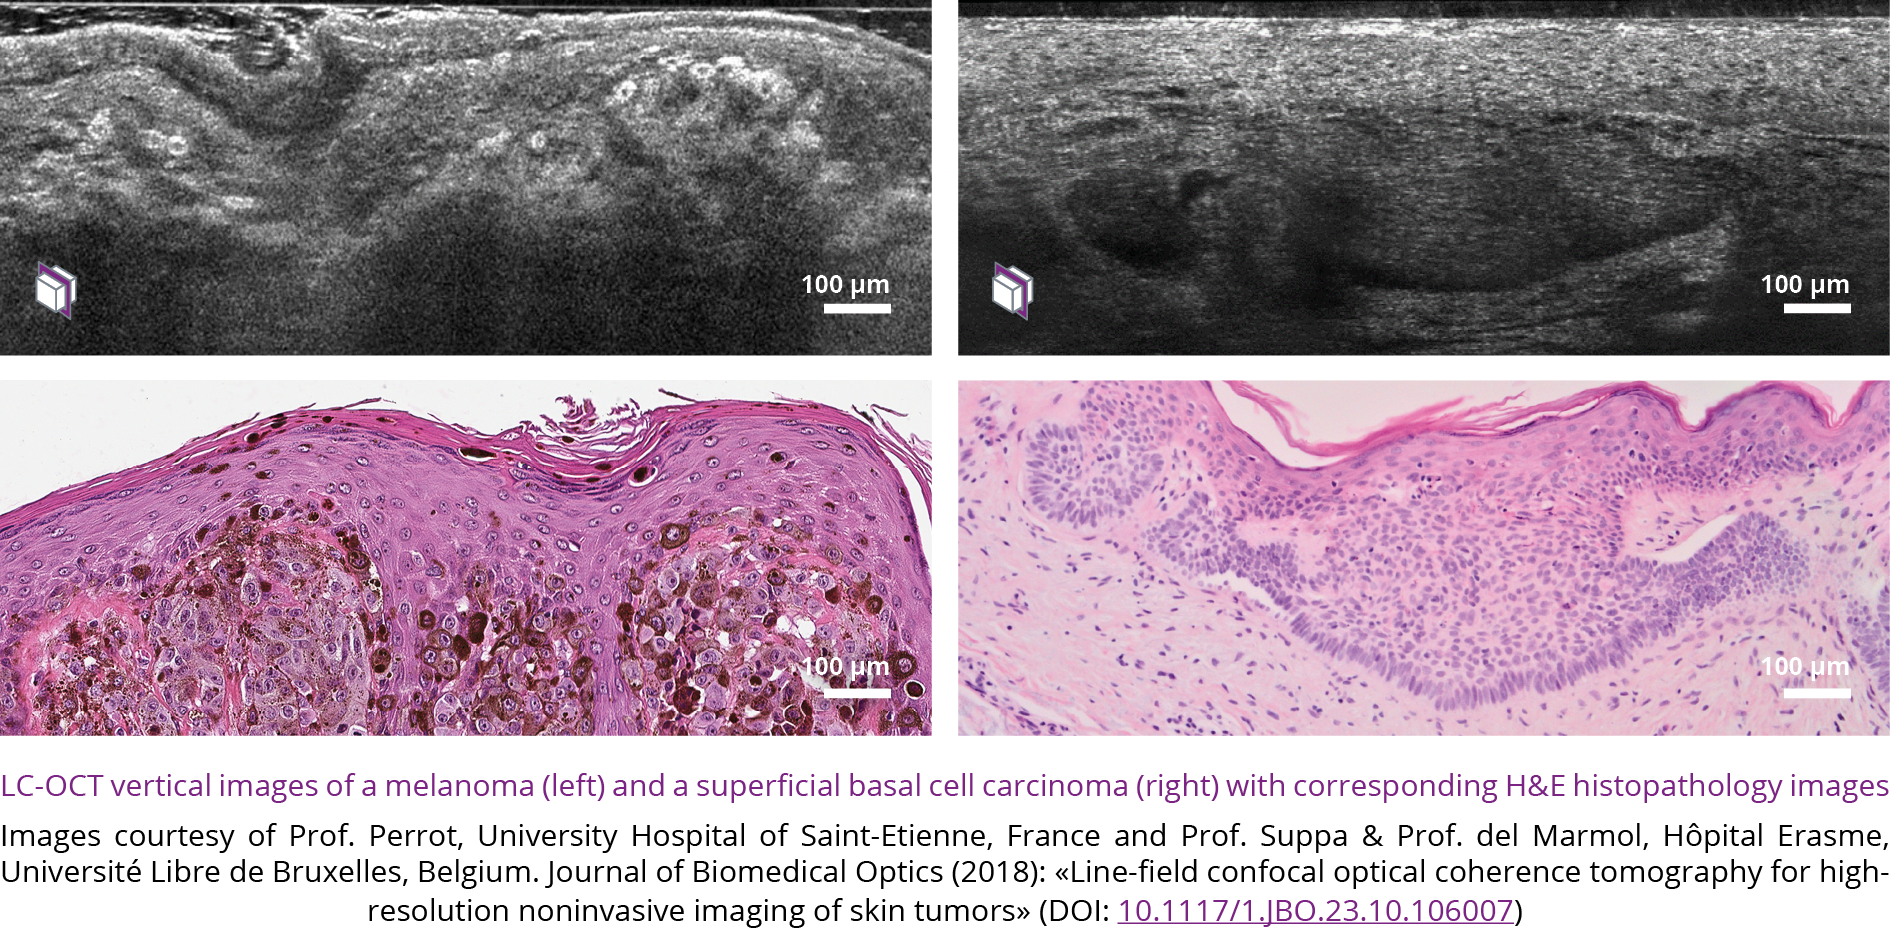

Validation of the potential of LC-OCT 2D imaging for the 2 main types of skin cancer: carcinoma and melanoma

First scientific publication: A. Dubois and al., “LC-OCT for high-resolution noninvasive imaging of skin tumors”, JBO 23, 106007